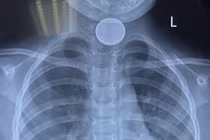

Các bác sĩ Bệnh viện Sản Nhi tỉnh Vĩnh Phúc đã gắp thành công một đồng xu kim loại có hình tròn đường kính 3cm từ trong thực quản cháu bé 4 tuổi ra ngoài.

BVĐK Xuyên Á vừa tiếp nhận bé gái 2 tuổi nuốt phải chiếc nhẫn vàng đeo trên ngón tay, khiến dị vật trôi vào thực quản, gây khó thở, sặc sụa. Một bé trai khác 4 tuổi cũng phải cấp cứu vì hóc đồng xu…

Trong lúc cầm chơi đồng xu, bé L. 5 tuổi (bé gái), ngụ tại huyện Hóc Môn, TPHCM đã bỏ đồng xu vào miệng và bị mắc tại thực quản, được các bác sĩ của Trung tâm Nội soi BV Đa Khoa Xuyên Á gắp ra thành công – TS.BS Nguyễn Văn Châu, Tổng Giám đốc BV Đa khoa Xuyên Á vừa cho biết.